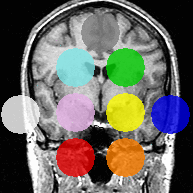

The second experiment includes real MRI images, in which AMF automatically segments the major brain compartments as well as subcortical structures. Due to the LogOdds parametrization, our method naturally evolves families of curves.